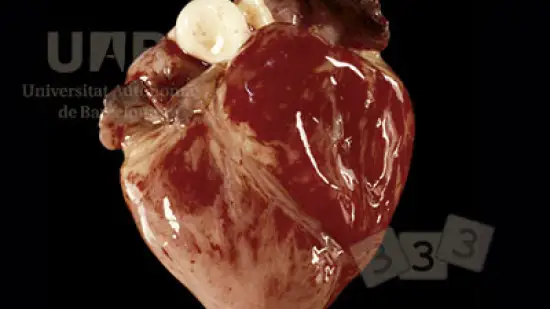

Laquelle des infections suivantes est associée à cette lésion ?